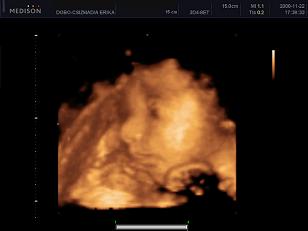

A papíron lévő adatok:

BPD: 84mm

HC: 301 mm

AC: 268 mm

FL: 58 mm

Na és a nap híre: eldőlt, legalábbis a mostani doki véleménye szerint, hogy a rózsaszín avagy a kék felé fog dőlni a mérleg nyelve:

úgy tűnik Bori/Borbála/Borcsa/Borka növekedik a pocóban